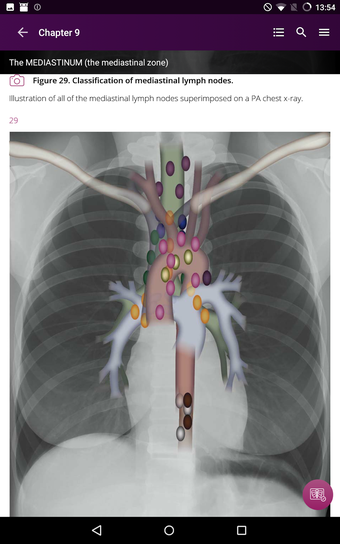

Radioloji'yi Keşfet: Göğüs Röntgeni Yorumlama, göğüs röntgeninin yorumlanmasının anlaşılmasını artırmak için tasarlanmış bir eğitim uygulamasıdır ve doktorlar, tıp öğrencileri ve radyologlar tarafından kullanılması amaçlanmaktadır. Uygulama, en küçük detayları görüntülemek için yakınlaştırılabilecek yüksek kaliteli görüntüler ve her bulgunun önemini anlamanıza yardımcı olacak bir sesli yorum içerir.

Uygulamanın amacı, kullanıcıların farklı x-ışını bulgularını ve bunların bir hastalığın teşhisinde nasıl kullanılabileceğini daha iyi anlamalarına yardımcı olmaktır. Uygulama, göğüs röntgeni yorumlaması için gerekli çeşitli yapı taşlarını kapsayan 5 bölüme ayrılmıştır.